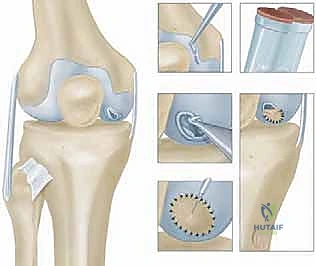

Stage 2: Implantation of Autologous Chondrocytes

Weeks later, the patient returns. Our cultured chondrocytes are ready. This is where we meticulously prepare the defect and implant the new cells.

Preoperative Planning (Stage 2)

- Cell Count Confirmation: Confirm with the cell culture lab that an adequate number of viable chondrocytes have been expanded for the size of the defect.

- Periosteal Patch Sizing: Based on the arthroscopic measurements from Stage 1, estimate the size of the periosteal patch needed.

- Instrument Tray: Ensure all specialized ACI instruments are available, including fine ophthalmic instruments, non-absorbable sutures (e.g., 6-0 Prolene or Vicryl), fibrin glue, and a specialized cell injection syringe.

Surgical Approach: Arthrotomy

"For ACI, we typically use a small knee arthrotomy. A midline incision is usually recommended, followed by a medial or lateral parapatellar arthrotomy, depending on the location of the chondral defect. For a medial femoral condyle lesion, a medial parapatellar arthrotomy provides direct access."

- Skin Incision: "Make a midline skin incision, approximately 6-8 cm in length, centered over the patella. Deepen through the subcutaneous tissue with electrocautery, carefully identifying and preserving the infrapatellar branch of the saphenous nerve if possible, to minimize postoperative numbness."

Arthrotomy: "Now, incise the retinaculum and joint capsule using either a medial or lateral parapatellar approach. For our medial femoral condyle lesion, we'll perform a medial parapatellar arthrotomy. Carefully reflect the patella laterally to expose the femoral condyle. Maintain careful hemostasis throughout."

Defect Preparation: Meticulous Débridement

"This is a critical step, fellows. We must prepare a pristine bed for our new chondrocytes. Any remaining unstable cartilage or fibrous tissue will compromise integration."

- Visualization and Exposure: "With the patella retracted, fully expose the chondral defect. Ensure the knee is positioned to provide optimal access to the lesion."

- Débridement: "Using a small curette, chondroplasty burr, or a sharp scalpel (e.g., a #15 blade), meticulously debride the defect down to healthy, stable subchondral bone."

- Remove all unstable cartilage: Any loose or fibrillated cartilage at the lesion margins must be removed. The goal is